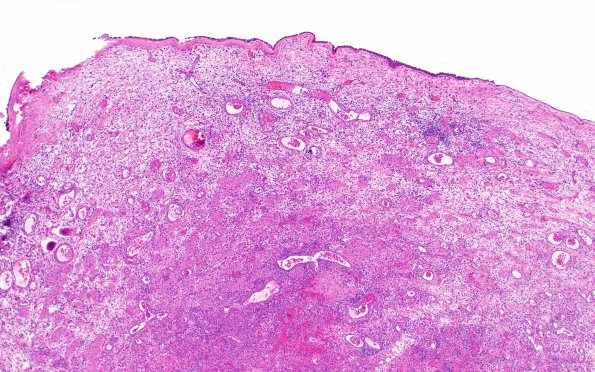

Washington University Experience | DEVELOPMENTAL MALFORMATIONS | Encephalocele - Nasal Glioma | 6B3Nasal glioma (Case 6) H&E 4X 2

6B3 There is a mostly intact epithelial lining to the surface of the mass surrounding a spongy aggregate of small vessels, inflammation and glioneuronal tissue. (H&E)